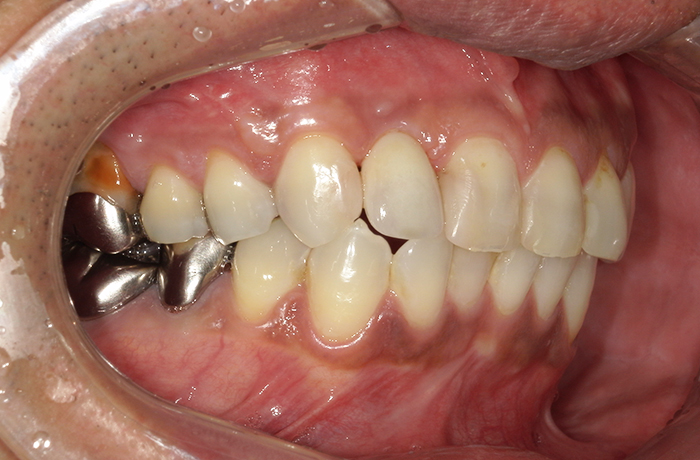

治療後

治療終了後の完成した口腔内と

レントゲン写真

インプラント周囲の骨レベルは安定し、歯肉の厚みとラインも自然に回復しました。

ジルコニアクラウンにより周囲歯と調和した色調を再現し、審美性と機能性の両立を実現することができました。